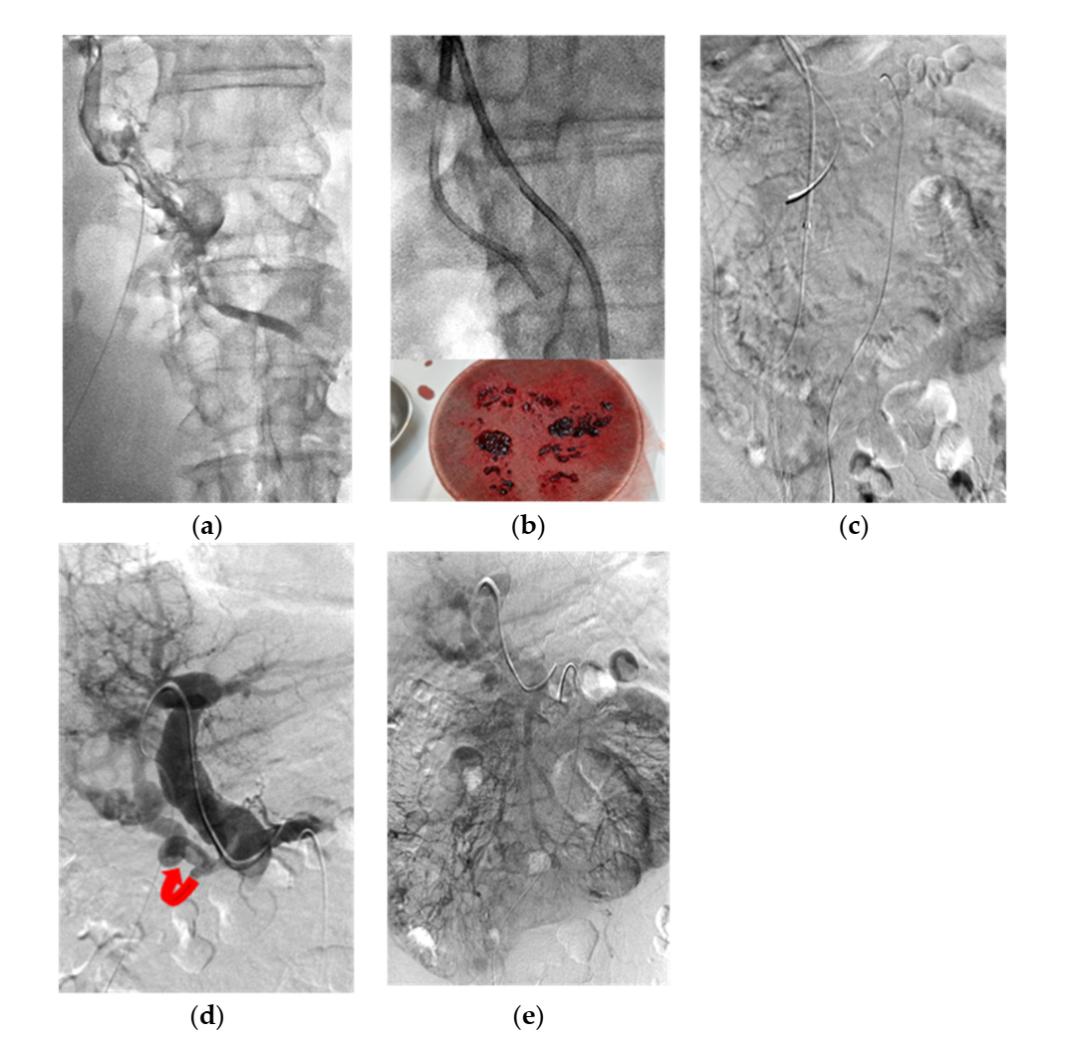

(图源自文献)

患者,男,58岁,5年前因MV血栓行节段回肠切除,主诉为腹痛4天。

a

经皮肝穿刺PV造影显示:PMVT累及近静脉弓处肝内PV、MV周围小静脉。

b

上部:X线透视显示:行导管(6F Envoy导管)抽吸。下部:抽吸出的新鲜性、陈旧性血栓。

c

肠系膜上动脉(SMA)血管造影(静脉期)显示:MV未显影。

d

经皮肝穿刺PV造影显示:经肝PV(持续6天)和经SMA(持续3天)途径反复球囊扩张、导管抽吸和连续输注UK,PV主干和肝内PV再通。曲线箭头:残留的PV海绵样变。

e

SMA血管造影(静脉期)显示:经治疗后,MV和PV显影。